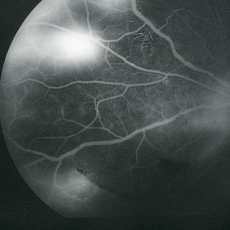

Late-phase fluorescein angiogram image of the left eye of a 23-year-old Vietnamese female with Eales Disease showing extensive dye leakage from multiple areas of NVE and from some NVD.

Imaging device: Topcon VT-50

Condition/keywords: Eales disease, FA late phase, fluorescein angiogram (FA), neovascularization elsewhere (NVE)